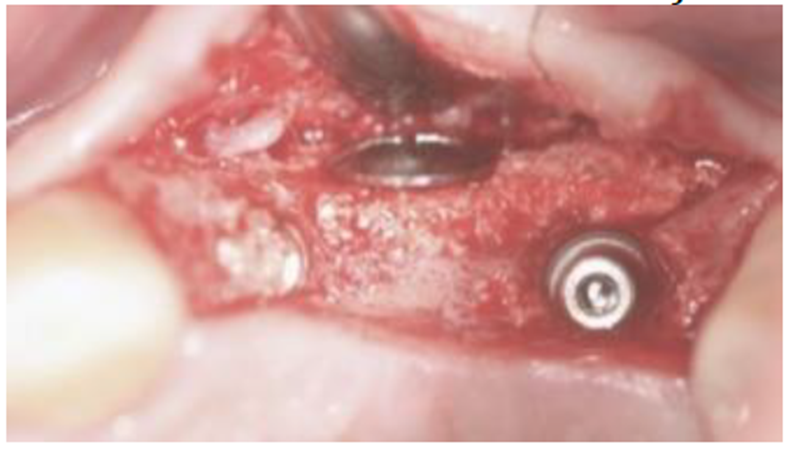

Após seis meses, os implantes foram reabertos e foi observado osso neoformado pelo material até o nível do parafuso, corrigindo o defeito em espessura e mantendo uma parede óssea vestibular espessa suficiente para manter o implante em função (Figura 9).